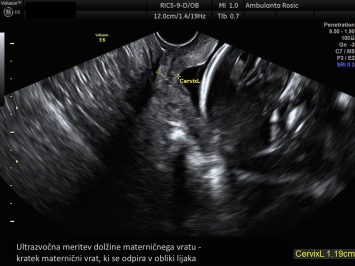

Zgodnja UZ potrditev nosečnosti Nuhalna svetlina in DHT z licenco FMF NIFTY test 3D/4D ultrazvočni pregled ploda Ultrazvočna meritev materničnega vratu Ultrazvočna kontrola plodove rasti, lege in teže Ultrazvočna kontrola ploda ter Dopplerska meritev pretokov Morfologija ploda Četverni hormonski test Streptokok B Kardiotokografija Galerija ultrazvočnih posnetkov